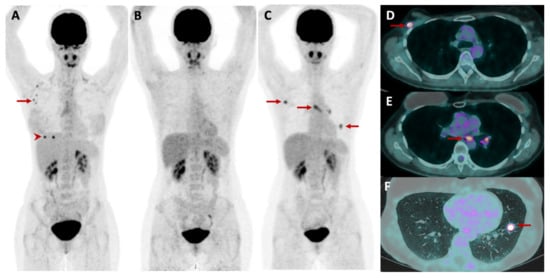

2.5.3. Metabolic and Receptor-Specific Imaging

2.5.4. Combined Modalities